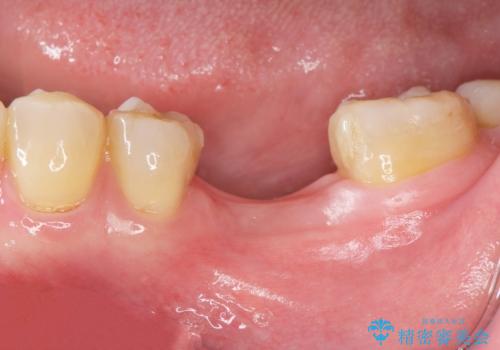

- 歯を破折により失い、インプラント治療を希望され来院されました。

インプラントを埋入し咬合機能を回復するとともに周囲の骨造成も同時に行っていきます。